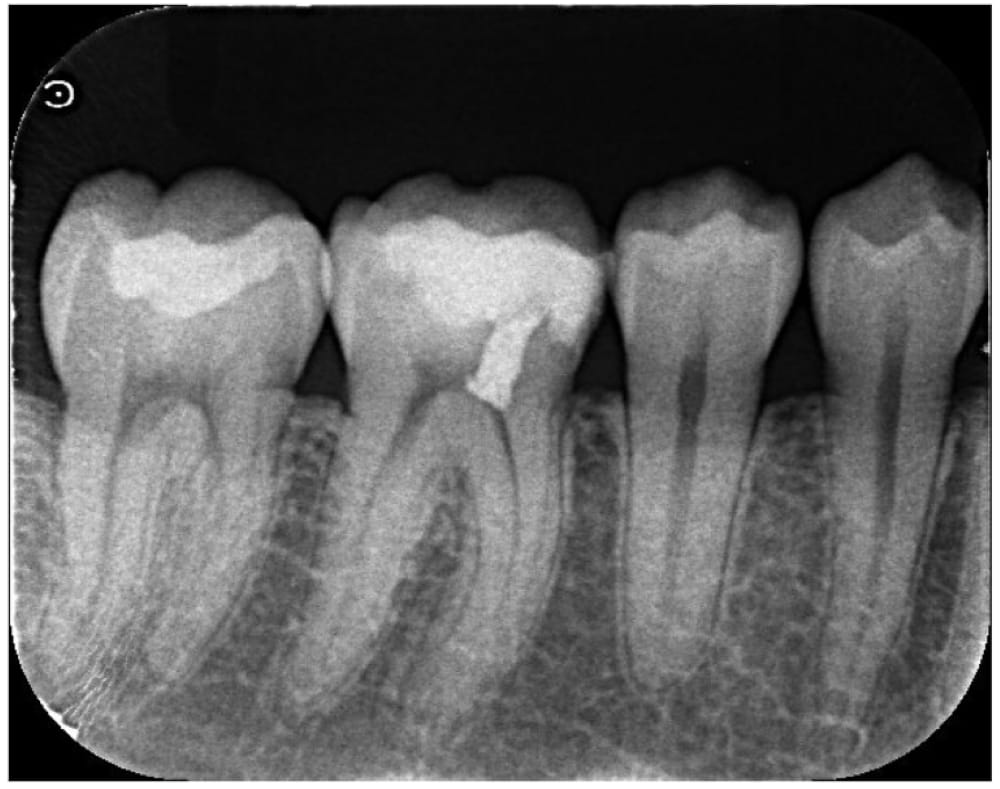

古い修復物の境目から虫歯が進行しており、レントゲン写真でも歯の神経に近接している状態でした。

歯髄検査の結果、歯髄は正常であることから、神経の保存は可能な状態でした。

また、虫歯の位置や歯列の位置からも、歯髄保存治療のアクセスが十分可能であることから、歯髄保存療法を実施することになりました。